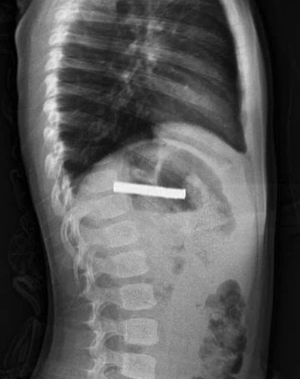

Evde rahatsızlandı, boğazından 19 mıknatıs çıktı!

Erzurum’da 3 yaşındaki bir çocuk evde bulunan 19 mıknatısı yuttu. Elazığ’daki Fırat Üniversitesi Hastanesi’nde Prof. Dr. Yaşar Doğan tarafından yapılan endoskopik operasyonla mıknatıslar çıkarıldı. Yemek borusu ve mide girişinde zedelenmeler oluşsa da küçük çocuğun sağlık durumunun iyi olduğu ve taburcu edildiği bildirildi.

Fırat Üniversitesi Çocuk Gastroenteroloji Hepatoloji ve Beslenme Bilim Dalı Başkanı Prof. Dr. Yaşar Doğan, çocuk hastanın yemek borusuna yapışmış 19 mıknatısı endoskopik yöntemle çıkardı.

Mıknatıslar uzun süre yemek borusunda takılı kaldığı için yemek borusu ve mide girişinde zedelenmeler olurken, çocuğun sağlık durumunun iyi olduğu ve taburcu edildiği öğrenildi.